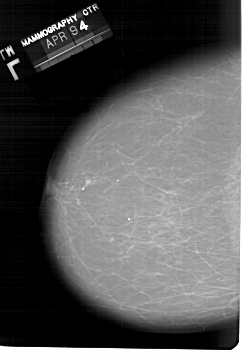

A_1331_1.LEFT_MLO

LEFT_MLO LINES 6871 PIXELS_PER_LINE 4231 BITS_PER_PIXEL 12 RESOLUTION 43.5 NON_OVERLAY